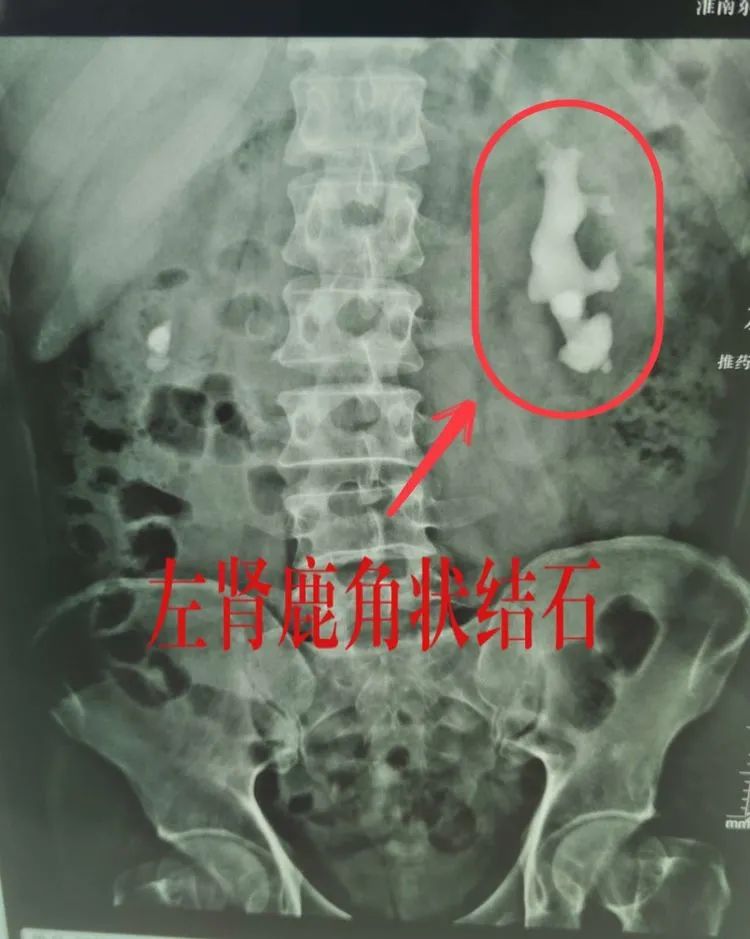

以经皮肾镜钬激光碎石治疗左肾结石为例,体外碎石的排石等待时间较长,而开放式手术创伤大,比较之下钬激光碎石创伤小、恢复快,就具有明显的优势。还有输尿管硬镜、软镜等多种微创诊疗方式,都可以让患者的结石无所遁形。